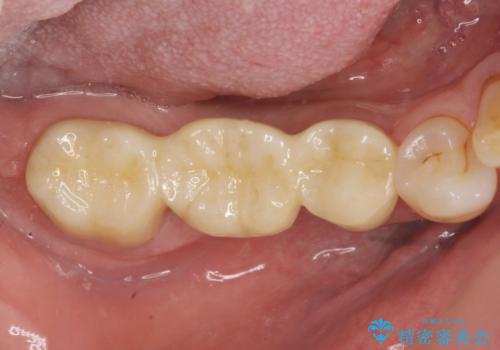

歯の破折 フルジルコニアブリッジ補綴

- 銀歯がダツリし、支える歯が破れている状態で抜歯を余儀なくされました。

短期間での咬合昨日の回復、手術を希望されなかったのでブリッジによる咬合機能回復を計画します。

かみ合わせが強いのでフルジルコニアクラウンベレッツァを用いたブリッジを製作。

- 24万円(仮歯・フルジルコニアクラウン×3)費用は治療当時の料金となります